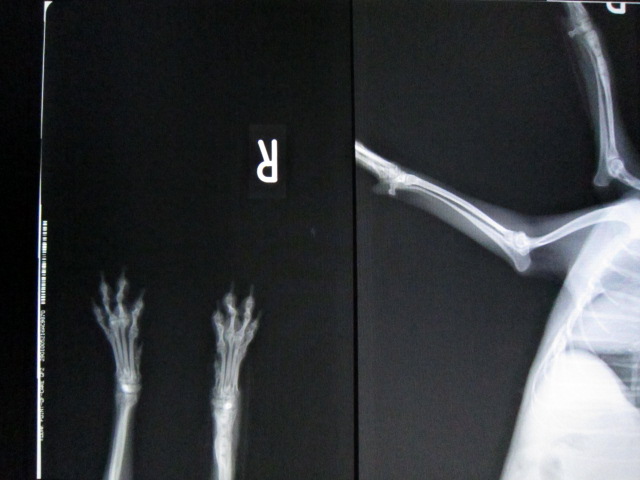

術前のレントゲンです。

右前肢橈尺骨遠位端骨折です。